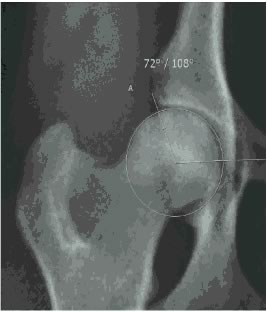

Para a realização de um diagnóstico seguro, é necessário realizar um exame de raio-x que é realizado com o animal em decúbito dorsal e com as patas traseiras esticadas para trás.

Após o resultado do exame radiográfico, o médico veterinário irá avaliar este exame e definir em qual categoria o animal se encontra.